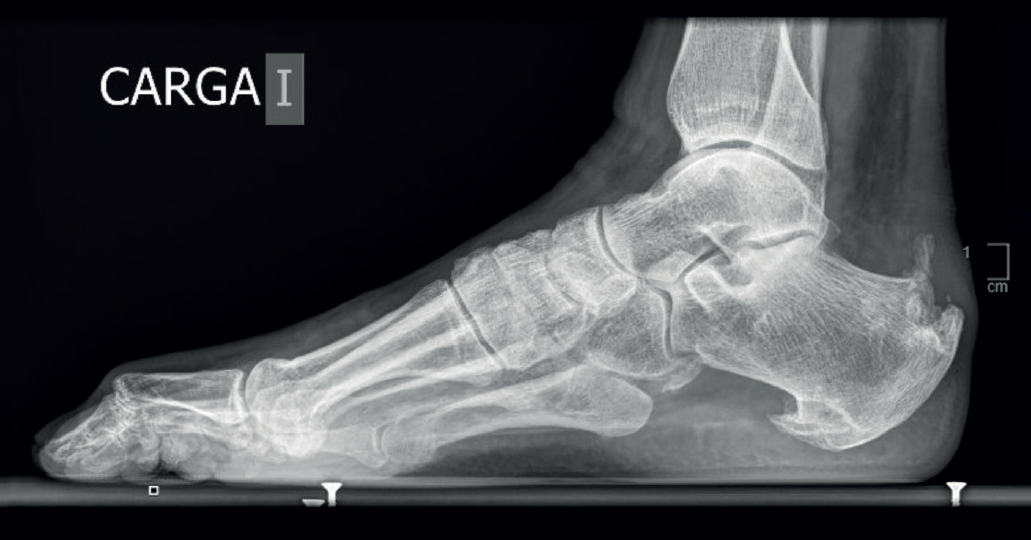

Figura 5. Radiografía lateral en carga del paciente de la Figura 4: obsérvese la ocupación del triángulo de Kager, la presencia de espolones óseos y de una calcificación intratendinosa. Se aprecia también el aumento del espesor de la sombra del tendón de Aquiles, demostrativo del engrosamiento tendinoso y el espolón plantar expresión de la alteración del sistema aquíleo calcáneo plantar.

- Radiografía: se recomienda una radiografía de perfil en carga para descartar calcificaciones intratendinosas, deformidad de Haglund(3) y bursitis retroaquíleas –visualizadas como una alteración del triángulo de Kager(28) (Figura 5)–, así como una radiografía anteroposterior de tobillo y de pies en carga y una proyección de Saltzman para el estudio de posibles deformidades axiales del pie(2,29).